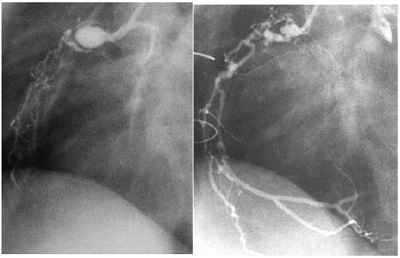

急性期の冠動脈炎による冠動脈の壁が破壊され、冠動脈が拡大し、瘤(こぶ)ができます(冠動脈瘤)。冠動脈瘤の大きさも軽度の拡大から巨大瘤(8mm以上)(図1)まで程度に差があります。

図1 川崎病による巨大冠動脈瘤

左図:右冠動脈瘤、右図:左冠動脈流